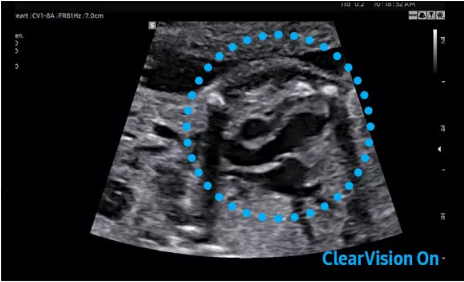

2D成像方面,Hera i10集成了包括ShadowHDR?、HQ-Vision?、ClearVision等多項具有三星“血統(tǒng)”的技術,加強了圖像的陰影抑制、減少偽影、緩和模糊區(qū)。